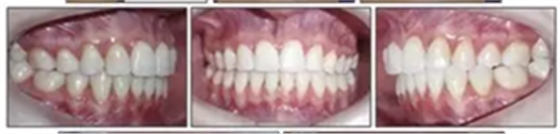

治療的總體目標(biāo)得以實(shí)現(xiàn)(圖8)??傊委煏r間為36個月。面部方面表現(xiàn)出充分的唇閉合和愉快的微笑。切牙運(yùn)動后有一些唇縮回。覆蓋和覆合良好,并且上下牙弓相協(xié)調(diào)(圖9)。I類磨牙關(guān)系得以實(shí)現(xiàn)。左側(cè)后牙反合得以矯正。下頜第二磨牙成功直立。

6年后治療結(jié)果保持穩(wěn)定(圖11,圖12 ; 圖13)??梢杂^察到穩(wěn)定的間隙關(guān)閉,正常的覆蓋和覆合,上下牙中線一致,微笑美觀。建議完美替代了拔除的側(cè)切牙。正畸治療后進(jìn)行牙齒美白。